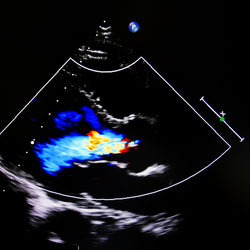

Quando invece la valvola mitralica non si chiude bene durante la fase di svuotamento del ventricolo sinistro, allora parte del sangue refluisce verso l’atrio di sinistra Si parla dunque di insufficienza della valvola mitrale L’insufficienza mitralica è una patologia molto frequente che può verificarsi a qualsiasi età. Si parla di insufficienza mitralica quando la valvola mitralica non chiude bene e durante la sistole del ventricolo sinistro una certa quantità di sangue ritorna indietro nell’atrio sinistro Significa che la valvola mitralica, durante la contrazione del ventricolo sinistro, lascia refluire in atrio sinistro una lieve Mi piace 2708. Che meccanismi ne governano l'apertura?.

Nel rigurgito della valvola mitrale, la valvola mitrale non si chiude ermeticamente Così, con ogni battito del cuore, il sangue dal ventricolo sinistro scorre indietro nell’atrio sinistro, invece che in avanti nell’ aorta Cause di rigurgito della valvola mitralica Il rigurgito della valvola mitrale può essere causato da molte cose, tra. Insufficienza mitralica L’insufficienza mitralica è una patologia caratterizzata da un difetto di chiusura della valvola mitrale che fa sì che parte del sangue pompato dal ventricolo sinistro refluisca nell’atrio sinistro invece che andare in aorta, provocando affaticamento e disturbi respiratori. Quando, invece, questa valvola non si chiude bene si ha la cosiddetta insufficienza mitralica, una situazione dove parte del sangue che dovrebbe essere pompato dal ventricolo sinistro nell’aorta rifluisce invece dentro all’atrio.

La valvola mitrale si apre per consentire al sangue dell’atrio sinistro di riempire il ventricolo sinistro, e di chiudersi quando il ventricolo sinistro si contrae per pompare il sangue nell’aorta Quando la valvola mitrale non si chiude completamente, parte del sangue rifluisce nell’atrio sinistro, detto rigurgito. Questo può essere causa di palpitazioni (sensazione che il cuore perda un battito o batta troppo forte o troppo veloce), fiato corto,. Nelle insufficienze valvolari invece, le camere cardiache interessate ricevono una quantità eccessiva di sangue, dovuta al rigurgito attraverso la valvola che chiude in maniera imperfetta Non dovendo vincere un'aumentata resistenza esse non hanno bisogno di aumentare lo spessore delle loro pareti e reagiscono al sovraccarico di volume.